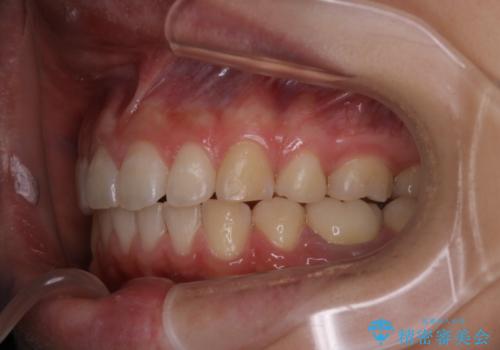

八重歯と形の悪い前歯 矯正治療とセラミック治療